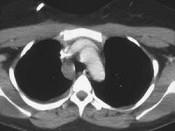

男,33岁,车祸后10余天,请结合影像学检查,选出最可能的诊断 ( )A.纵隔畸胎瘤B.胸内甲状腺肿C.胸腺瘤D.淋巴瘤E.纵隔血肿

问题 男,33岁,车祸后10余天,请结合影像学检查,选出最可能的诊断 ( )

选项 A.纵隔畸胎瘤 B.胸内甲状腺肿 C.胸腺瘤 D.淋巴瘤 E.纵隔血肿

答案 E